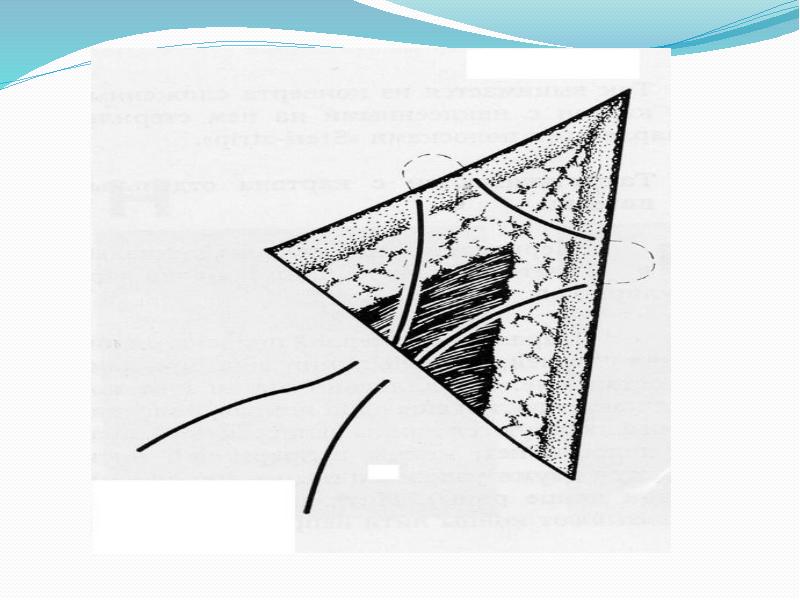

- 42. Угловой сопоставляющий шов Кровоснабжение треугольных участков кожи, как правило, снижено. Поэтому

- 43. Схема проведения лигатуры при наложении узлового углового шва.